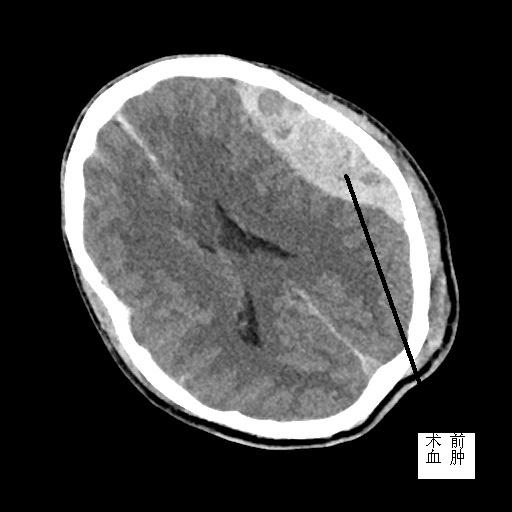

患者潘先生,因騎車(chē)摔倒入院搶救。入院時(shí),潘先生神志已模糊,無(wú)法對(duì)答,經(jīng)相關(guān)檢驗(yàn)檢查,提示顱內(nèi)多發(fā)損傷,我院神經(jīng)外科MDT團(tuán)隊(duì)緊急會(huì)診,評(píng)估病情,并給予緊急處理。潘先生情況不容樂(lè)觀,顱內(nèi)壓明顯增加,出現(xiàn)腦疝,若不緊急手術(shù),顱內(nèi)壓可進(jìn)一步增加,到時(shí)將造成不可逆腦損傷,甚至危及生命。家屬了解到我院與福醫(yī)大附二院建立神經(jīng)外科專(zhuān)科聯(lián)盟,每天有專(zhuān)家值班在線指導(dǎo),可緊急來(lái)院幫扶搶救,遂放棄轉(zhuǎn)院,決定入院治療。

接到信息,當(dāng)日值班專(zhuān)家黃金鐘主任立即趕來(lái)。為與病魔賽跑,黃主任爭(zhēng)分奪秒利用途中時(shí)間,在了解潘先生病情的基礎(chǔ)上與我院專(zhuān)家討論病情、評(píng)估手術(shù)相關(guān)風(fēng)險(xiǎn)、確定手術(shù)方案……同時(shí),我院神經(jīng)外科完善術(shù)前檢查、備血、剃頭等術(shù)前準(zhǔn)備,確保專(zhuān)家到位后,潘先生能第一時(shí)間送入手術(shù)室。

經(jīng)黃主任與我院專(zhuān)家合力搶救,潘先生手術(shù)順利,轉(zhuǎn)入ICU進(jìn)一步治療。術(shù)后,潘先生意識(shí)逐漸清醒,目前在福醫(yī)大附二院神經(jīng)外科專(zhuān)家參與下進(jìn)行后續(xù)康復(fù)治療。